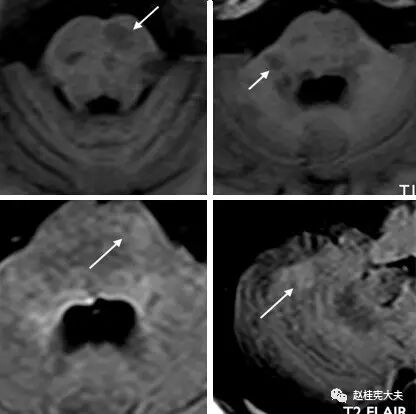

图10. (上图)T1、(下图)T2 FLAIR像示:病灶累及脑桥、延髓、双侧小脑。